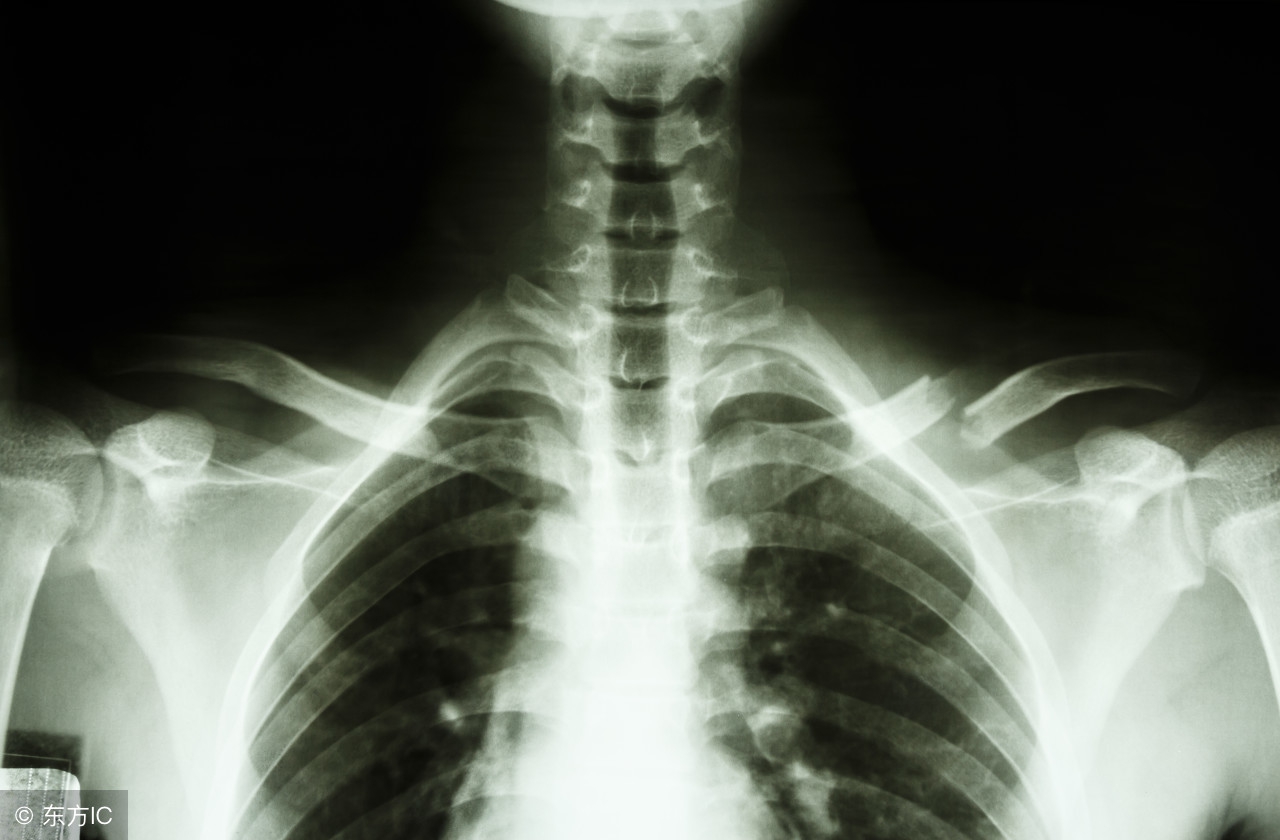

三、怀疑锁骨骨折了,需要做哪些检查?

第一时间怀疑骨折了,肯定要到专科医院就诊,早期处理避免病情加重;

医生会询问患者或者患儿详细的受伤病史,同时辅助查体,必要时会给你安排X线检查明确骨折的类型以及严重程度。

对于两岁的小孩,发生锁骨“青枝骨折”的可能性较大,X线可以帮助我们确诊!